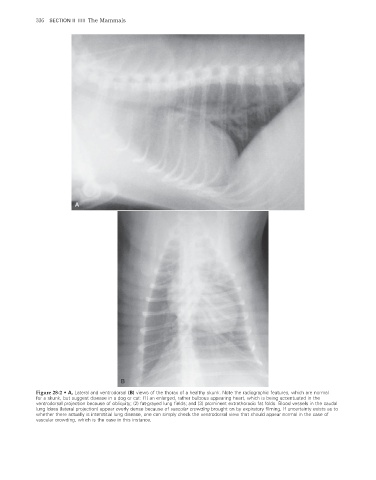

Figure 28-2 • A, Lateral and ventrodorsal (B) views of the thorax of a healthy skunk. Note the radiographic features, which are normal

for a skunk, but suggest disease in a dog or cat: (1) an enlarged, rather bulbous appearing heart, which is being accentuated in the

ventrodorsal projection because of obliquity; (2) fat-grayed lung fields; and (3) prominent extrathoracic fat folds. Blood vessels in the caudal

lung lobes (lateral projection) appear overly dense because of vascular crowding brought on by expiratory filming. If uncertainty exists as to

whether there actually is interstitial lung disease, one can simply check the ventrodorsal view that should appear normal in the case of

vascular crowding, which is the case in this instance.